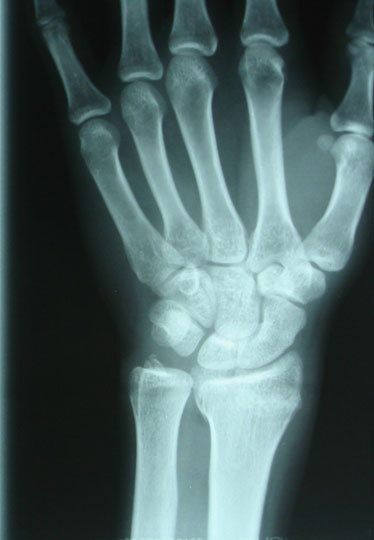

Les grandes avancées de la médecine

Ce diaporama permet de retracer une partie de l’histoire de la médecine à travers ses grandes avancées techniques ou ses découvertes. De l’invention du stéthoscope à l’arrivée de l’IRM, une vingtaine d’images accompagnées d’informations viendront en support pour alimenter une discussion autour de la vision de chacun sur ces progrès médicaux qui ont changé notre quotidien. N'oubliez pas de "dezipper" le diaporama avant de le lancer.

'name' => 'Rayon X...'